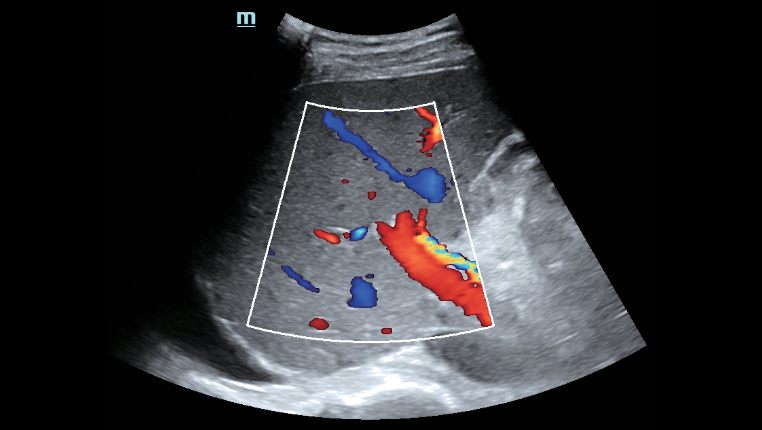

? ??? ?? ???? ???? ?? ???? Hepatus? ? ??? ??? ???? ??? ??? ?????. ???? ????? ??? ? ?? ??? ???? ????? ? ?? ???? ? ?? ??? ??? ??? ?????.

??? ???? ?? ? ??? ? ? ???? ?? ??, ??, ???? ? ?? ??? ??? ? ????. ?? ?? ???? ?????.

- ??? ?? ? ??

- ?? ?? ? ??

- ?? ??